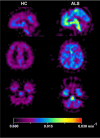

The reactive astrocytes manifest molecular, structural, and functional remodeling in injury, infection, or diseases of the CNS, which play a critical role in the pathological mechanism of neurological diseases. A growing need exists for dependable approach to better characterize the activation of astrocyte in vivo. As an advanced molecular imaging technology, positron emission tomography (PET) has the potential for visualizing biological activities at the cellular levels. In the review, we summarized the PET visualization strategies for reactive astrocytes and discussed the applications of astrocyte PET imaging in neurological diseases. Future studies are needed to pay more attention to the development of specific imaging agents for astrocytes and further improve our exploration of reactive astrocytes in various diseases.

Keywords: Alzheimer’s disease (AD); Amyotrophic lateral sclerosis (ALS); Monoamine oxidases-B (MAO-B); Multiple sclerosis (MS); Parkinson’s disease (PD); Positron emission tomography (PET); Reactive astrocytes.